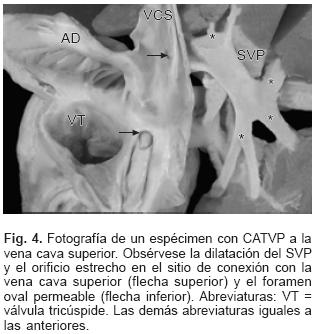

En todos los especímenes el SVP estuvo independiente, separado del atrio izquierdo y ubicado por detrás y un poco por encima de esta cámara cardíaca incompleta y pequeña (Figs. 1 y 2). El SVP se continuó con un vaso colector que siguió diferentes trayectos según el sitio de conexión anómala; en el tipo a vena cava superior el colector ascendió por detrás del bronquio derecho o del izquierdo según la posición de esa vena; en dos especímenes la obstrucción del colector fue intrínseca por estrechez del mismo en el sitio de su desembocadura (Figs. 3A y 4) y en un espécimen el colector siguió un trayecto anómalo entre la rama derecha de la arteria pulmonar y el bronquio derecho lo que provocó obstrucción extrínseca en el mismo (Fig. 3B). En el sitio de conexión anómala a la vena vertical el SVP recibió las venas de ambos pulmones y a través de un colector corto se continuó con la vena vertical ubicada del lado izquierdo, ésta a su vez lo hizo con el tronco venoso braquiocefálico izquierdo que desembocó en la vena cava superior y ésta en el atrio derecho (Fig. 5); en un espécimen existió obstrucción intrínseca en la vena vertical (Fig. 6).